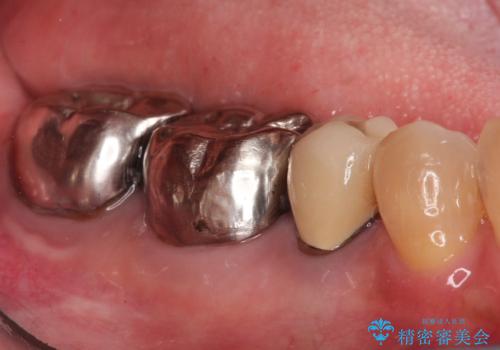

- 「銀歯が目立つのがずっと気になっていた」とのご相談で来院されました。左下の奥歯(5・6・7番)には保険治療で入れた銀色の被せ物が入っており、笑ったときや口を開けた際に見えるのが気になるとのことでした。

歯ぐきの状態やかみ合わせを確認したところ、被せ物の適合に大きな問題はなかったものの、審美的な観点から、白く自然な見た目のセラミッククラウンにやりかえることで、より快適に過ごしていただけると判断しました。セラミックは金属を使わないため、見た目が自然で、金属アレルギーの心配もない素材です。長期的な予後の安定も見込めるため、審美と機能を両立した治療計画をご提案しました。